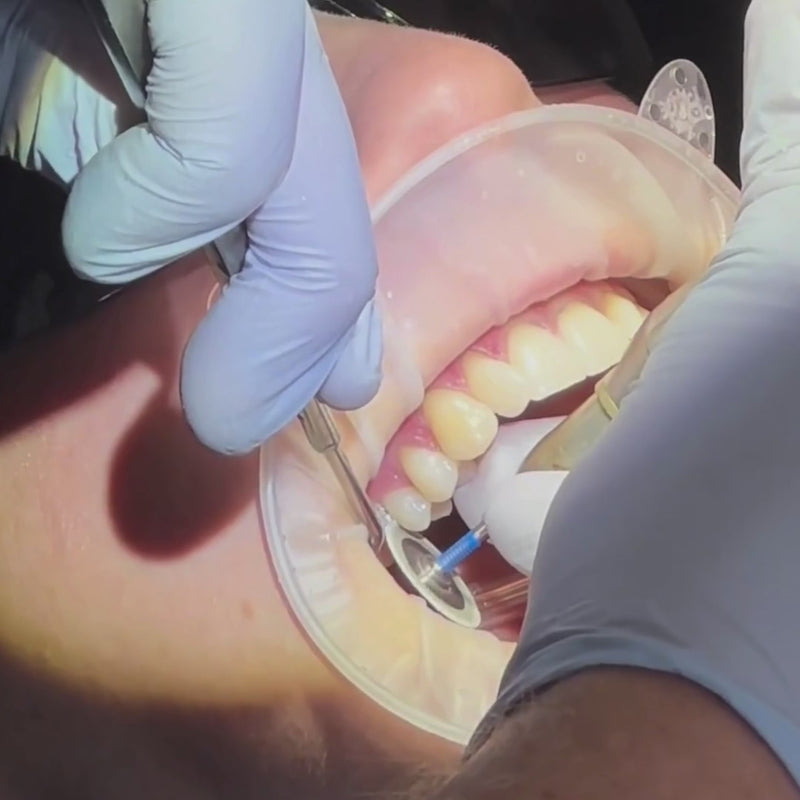

IPR (Interproximal Reduction) is a very common orthodontic procedure where a tiny amount of enamel is gently polished from the sides of selected teeth. This creates a little extra space without needing to remove any teeth.

It’s often used to help relieve crowding, improve alignment, or allow the teeth to move more effectively during clear aligner treatment. The procedure is minimally invasive, done with specialised tools, and only removes a very small amount of enamel — much less than the thickness of a fingernail.

Modern orthodontics now uses IPR instead of extracting teeth in most mild crowding cases. It’s usually done on less visible teeth, so it doesn’t affect appearance, and it does not weaken the teeth.

Afterwards, the surfaces are smoothed and polished, and most patients experience little to no discomfort.